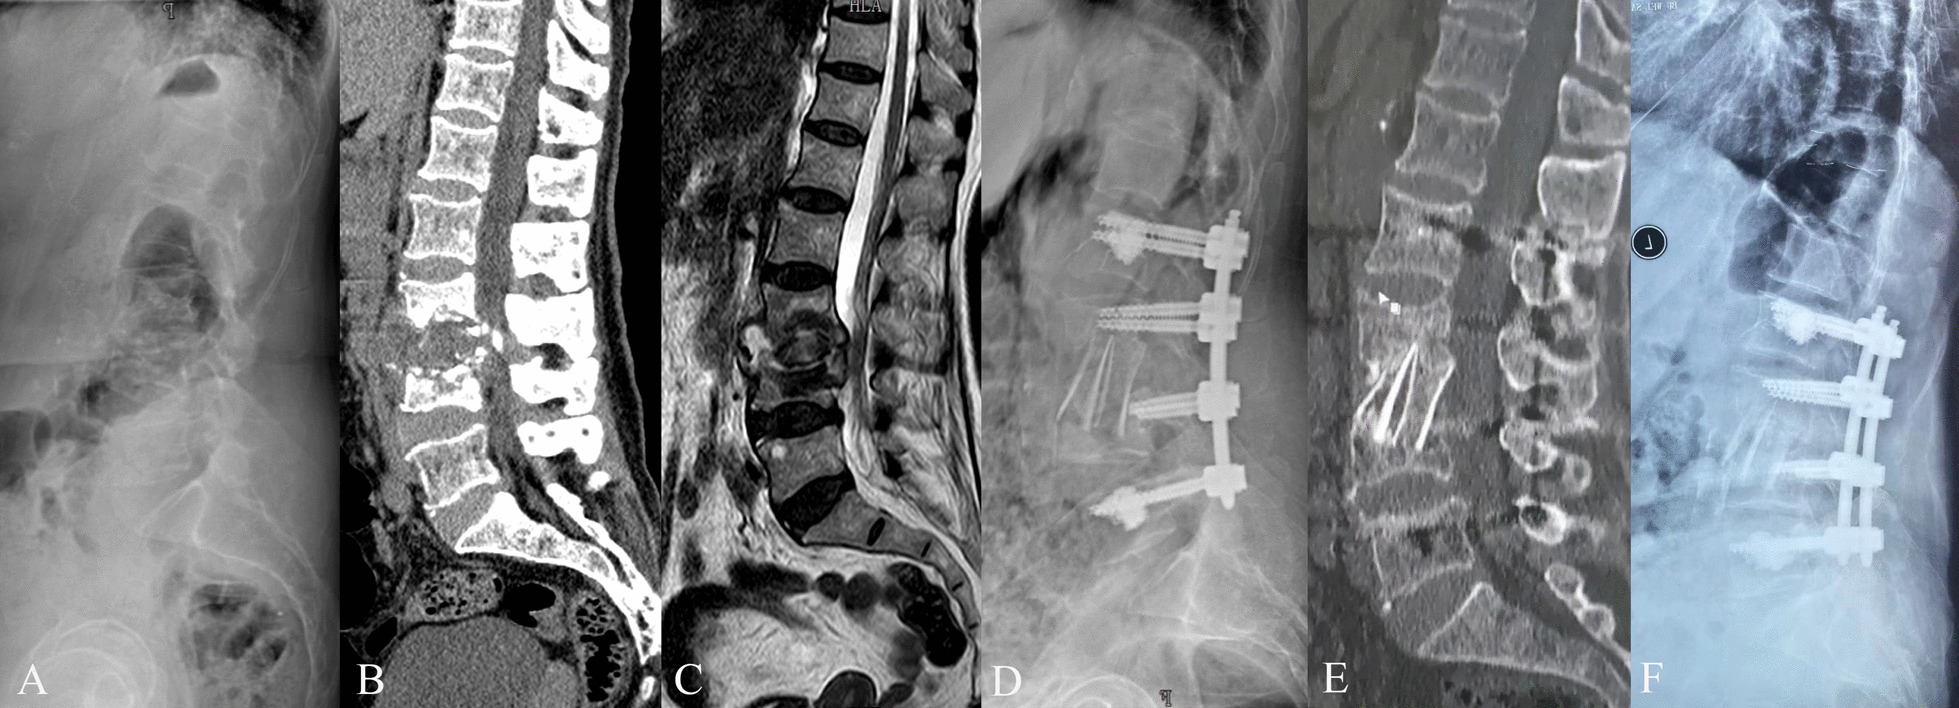

Fig. 1.

A 81-year-old female with L3-4 tuberculosis and severe osteoporosis. The patient underwent one-stage anterior debridement, bone grafting, and posterior percutaneous fixation with cement-augmented pedicle screws. A–C Preoperative lateral X-ray, sagittal CT scan, and sagittal MRI scan images demonstrated bone destruction and intraspinal abscess. D Postoperative lateral X-ray image. E Sagittal CT scan at 17-month follow-up. F Postoperative X-ray image at 30-month follow-up